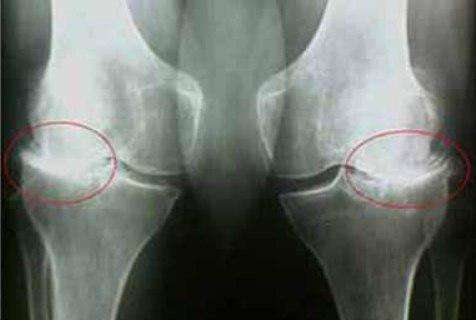

Εμένα το Turmeric Curcumin με βοήθησε πολύ! Πρήστηκε το γόνατο δεν μπορούσα να λυγίσω το πόδι μου. Ο πατέρας μου μου έφερε από κάπου το και Turmeric Curcumin Δόξα το Θεό! Δείτε την διαφορά:

Εμένα το Turmeric Curcuminμε βοήθησε πολύ! Πρήστηκε το γόνατο δεν μπορούσα να λυγίσω το πόδι μου. Ο πατέρας μου μου έφερε από κάπου το και Turmeric Curcumin Δόξα το Θεό! Δείτε την διαφορά: